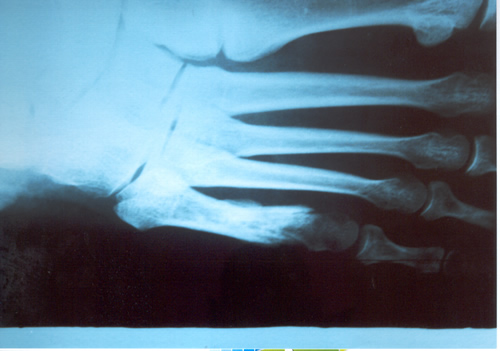

FRACTURA DEL QUINTO METATARSIANO

Generalmente la informamos como fractura de la cola del quinto metatarsiano, porque allí es el lugar de mayor frecuencia, especialmente en el deportista saltador. En nuestro estudio estadístico y para el libro de Traumatología en el Futbol ( edición 2005 Ed Akadia,)

observamos que la mayor cantidad de estas fracturas, fueron padecidas por los defensores centrales , atribuible esto al mecanismo de acción en el salto en ambas áreas, correspondiente a la función de dicho jugador. El caer, frecuentemente se genera una torsión en supinación en el momento de apoyar con la cara externa del pié, ora en terrenos desiguales ó bien con pérdida de la estabilidad en el aire, debido a la fricción con el contrincante.

Dicha caída desarticulada produce un esguince de antepié, con impacto sobre la cola del quinto y fractura secuelar. Puede escucharse ruido con dolor puntual, por lo que el jugador abandona el campo de juego.

En la generalidad de los casos, con una inmovilidad adecuada sin cargar el peso del cuerpo por 45 días suele consolidar la fractura. Depende del trazo de la fractura y en que lugar está ubicada en el hueso Dicho metarsiano presenta una irrigación sanguínea deficiente y es quizás la causa importante que impide consolidaciones seguras y en poco tiempo. Aún mas, si ocurre en un pié cavo varo, es decir en un pié con mucho arco interno distinto ú opuesto al apoyo anatómico del pié plano. Este es el jugador que padece esguinces a repetición de tobillo por exceso de arco del pié.

Si la fractura se ubica en el tercio medio de la diáfisis del hueso , ya no en la cola del quinto, el tratamiento incruento generalmente es exitoso. En nuestro caso y para esta patología nos estamos ocupando sólo de la cola del quinto.